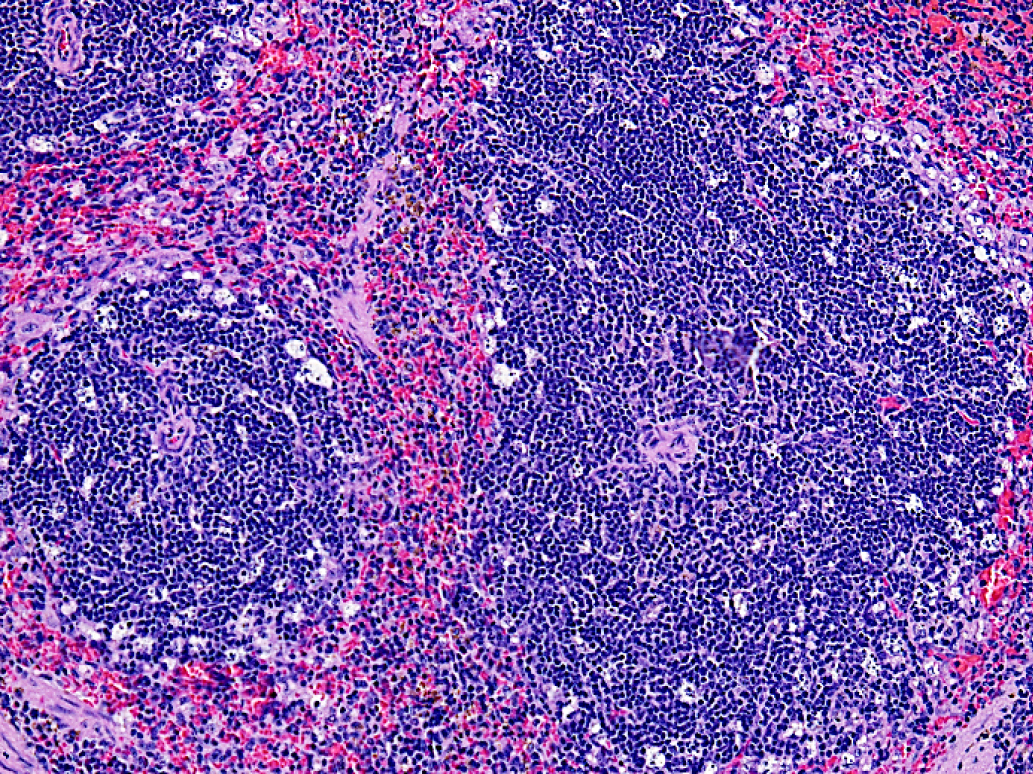

Fig. 4. A fragment of the spleen of an experimental mouse after administration of 80 mg/kg 5'- noraristeromycin. Hematoxylin–eosin staining. 200× magnification

Death of multiple lymphoid cells at the periphery of white pulp follicles was detected in the spleens of the experimental animals (Fig. 4).